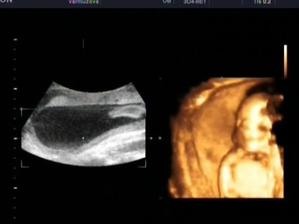

17.12. 4D ultrazvuk + video a konecne vime, ze jsi holcicka!!!!! nejkrasnejsi darecek k mym narozeninam 🙂